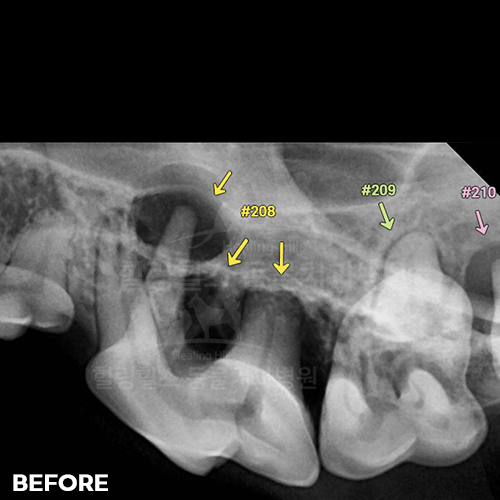

[강아지발치] 잇몸뼈가 녹은 구멍에 자기잇몸뼈가 튼튼하게 재생되어 채워졌어 - 강아지치아발치 2년 후 구강X-ray 비교! -

2025.11.26